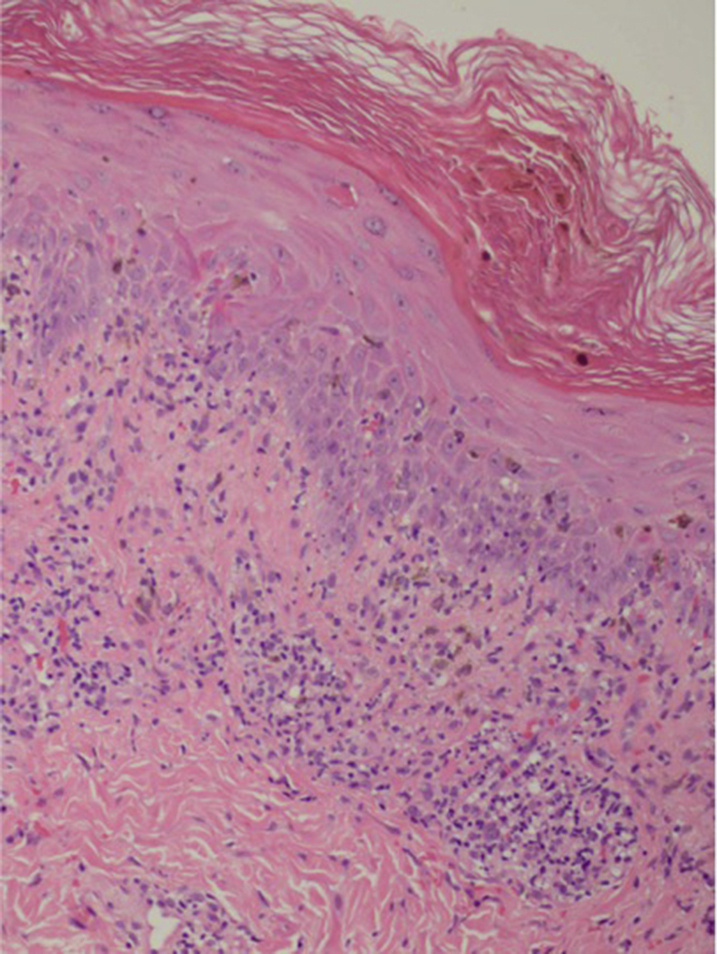

The patient was treated empirically for syphilis infection with benzathine penicillin G. Laboratory evaluation revealed that he was negative for rapid plasmin reagin, his CD4 count was 310 cells/mm3, and he had an undetectable viral load. A skin biopsy was performed that demonstrated lichenoid interface dermatitis with parakeratosis and dyskeratosis, a mononuclear perivascular infiltrate, and eosinophils consistent with a lichenoid hypersensitivity reaction (Fig 3).

Fig 3.

Hematoxylin-eosin stain of punch biopsy.

LP is an inflammatory dermatosis that can be either idiopathic or associated with exogenous antigens, such as hepatitis C virus, vaccines, contact allergens, and medications.7 Compared with idiopathic LP, drug-induced LP (lichenoid drug eruption) more commonly presents in photo-distributed areas, sparing the wrists and lower legs and rarely involves the mucosa.7 Eosinophils, parakeratosis, and deep involvement of the lymphocytic infiltrate are characteristic histologic findings of lichenoid drug eruption. However, histologic staining alone cannot be reliably used to distinguish between drug-induced and idiopathic LP.8 Our patient had many clinical and histologic features of drug-induced LP, including sparing of the distal extremities and mucosa as well as presence of eosinophils on pathology. He also scored highly on the Naranjo scale, demonstrating probable causality between efavirenz and the adverse cutaneous reaction.9 His morphologic presentation of generalized giant annular LP is the first described in relation to drug exposure.